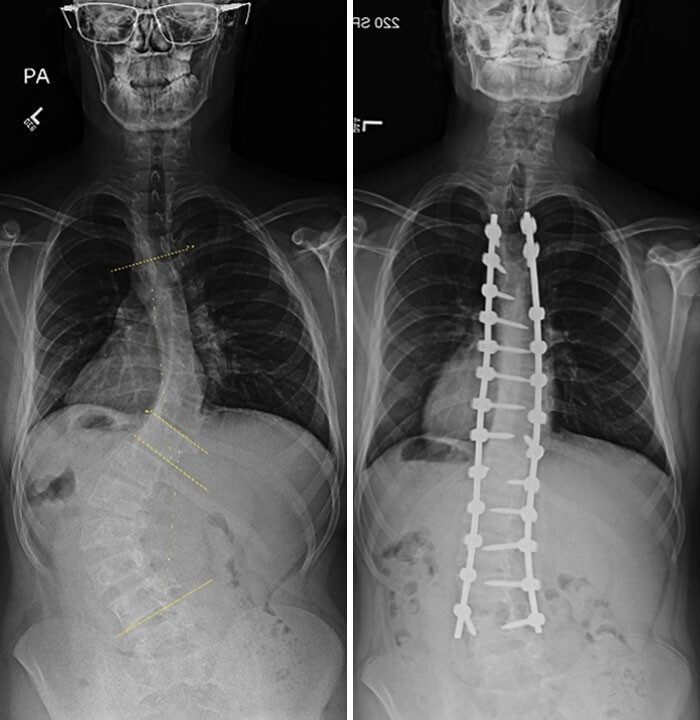

Операция по поводу искривления позвоночника: до и после